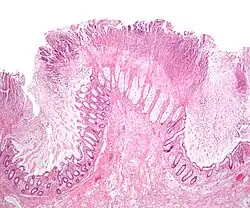

| A micrograph demonstrating cryptitis, a microscopic correlate of colitis. H&E stain. | |

An important investigation in the assessment of colitis is biopsy for histopathology. A very small piece of tissue (usually about 2mm) is removed from the bowel mucosa during endoscopy and examined under the microscope by a histopathologist. A biopsy report generally does not state the diagnosis, but should state any presence of chronic colitis, give an indication of disease activity, as well as state the presence of any epithelial damage (erosions and ulcerations).[6]

Histopathology findings generally associated with chronic colitis include:[6]

-

Crypt degeneration -

Crypt branching and other architectural distortions -

Paneth cell (pictured) or gastric metaplasia (only applies in the left colon and rectum)

Other findings include basal plasmacytosis and mucin depletion.[6] Histopathology findings generally associated with active colitis include:[6]

Neutrophilic cryptitis (neutrophils within crypt epithelium) -

Crypt abscesses (luminal neutrophilic aggregates) -

Gland destruction -

Ulceration (seen here as absence of epithelium, and granulation tissue with many fibroblasts)